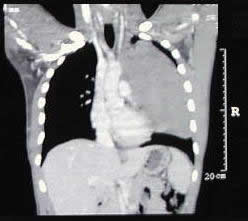

un paciente joven, con un gran tumor del mediastino anterosuperior de rápido

crecimiento, correlacionando su tamaño entre la radiografía

del tórax y los hallazgos tomográficos realizado 15 días

después, y las condiciones físicas al momento de su intervención,

con gran dificultad respiratoria.